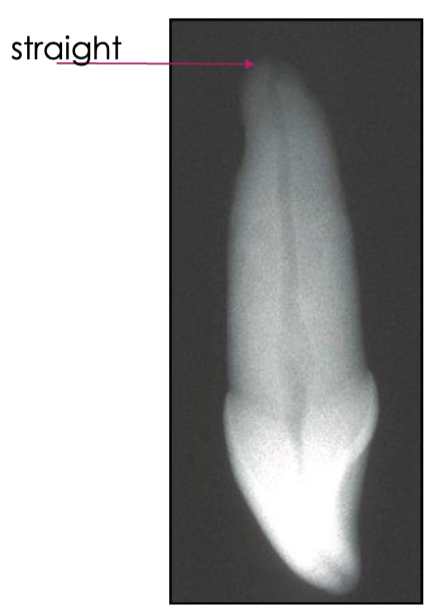

is this an example of straight line access

NO: need to open orifice (where red arrow is pointing) to be able to get straight line access

shape of the root of a central incisor

usually straight

canals of maxillary central incisors are usually ________

straight